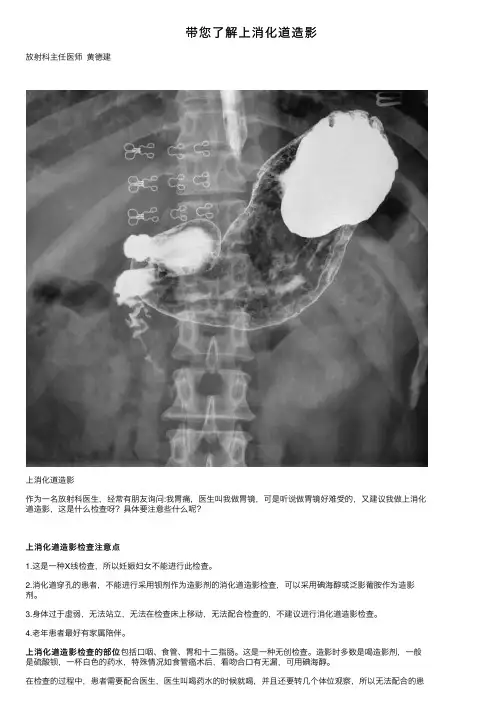

上消化道造影

作为⼀名放射科医⽣,经常有朋友询问:我胃痛,医⽣叫我做胃镜,可是听说做胃镜好难受的,⼜建议我做上消化道造影,这是什么检查呀?具体要注意些什么呢?

上消化道造影检查的部位

上消化道造影检查的部位包括⼝咽、⾷管、胃和⼗⼆指肠。

这是⼀种⽆创检查。

造影时多数是喝造影剂,⼀般是硫酸钡,⼀杯⽩⾊的药⽔,特殊情况如⾷管癌术后,看吻合⼝有⽆漏,可⽤碘海醇。

在检查的过程中,患者需要配合医⽣,医⽣叫喝药⽔的时候就喝,并且还要转⼏个体位观察,所以⽆法配合的患

者,这个检查就没法做了。

这个检查的原理主要是通过喝不透X线的硫酸钡,使得流过的通道显⽰出来,这样⾷管、胃的外观就显⽰出来,包括它们动态的变化都可以观察。

这种⽆创检查,对于患者来说,⼀般没什么痛苦,容易接受。

能够间接观察到胃的形态、⼤⼩、位置⼂蠕动及内部的黏膜情况。

可以诊断上消化道炎症,溃疡,较⼤的占位,功能性疾病等等,曾经是诊断上消化道疾病的重要检查。

胃镜检查可以很直观地观察到上消化道的内部微⼩病变,⽽上消化道造影可以观察到消化道的外观情况。

尤其适⽤于如贲门失弛缓症这种功能性的疾病。

因此,医⽣根据诊断需要,让患者选择胃镜或上消化道造影检查,或者两者都要做均是合理的。